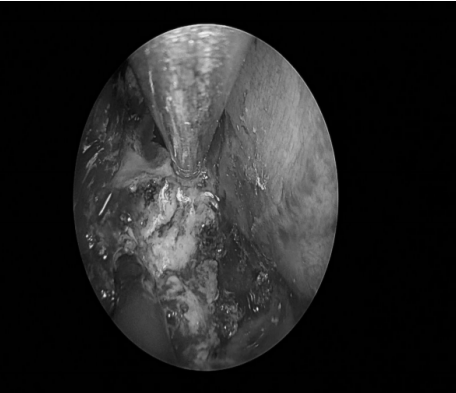

手术经过

术后病理:(颅底肿瘤)表皮样囊肿。(双侧鼻息肉) 息肉,嗜酸性粒细胞浸润<10% 背景炎细胞。

3、鼻内镜入路:包括经翼突入路、经上颌窦入路、经口入路。蝶骨翼突起于蝶骨体与蝶骨大翼交接处下方,分成翼内板和翼外板。翼内板和翼外板的前上部融合,下部分离形成翼切迹,与腭骨锥突连接。

翼内板和翼外板之间称为翼窝,为翼内肌的起始处。鼻内镜入路优点在于不损伤听力、颜面部无切口,但手术操作仍有许多困难,要求手术操作者磨除翼突时应十分熟悉翼腭窝、颞下窝的解剖结构。